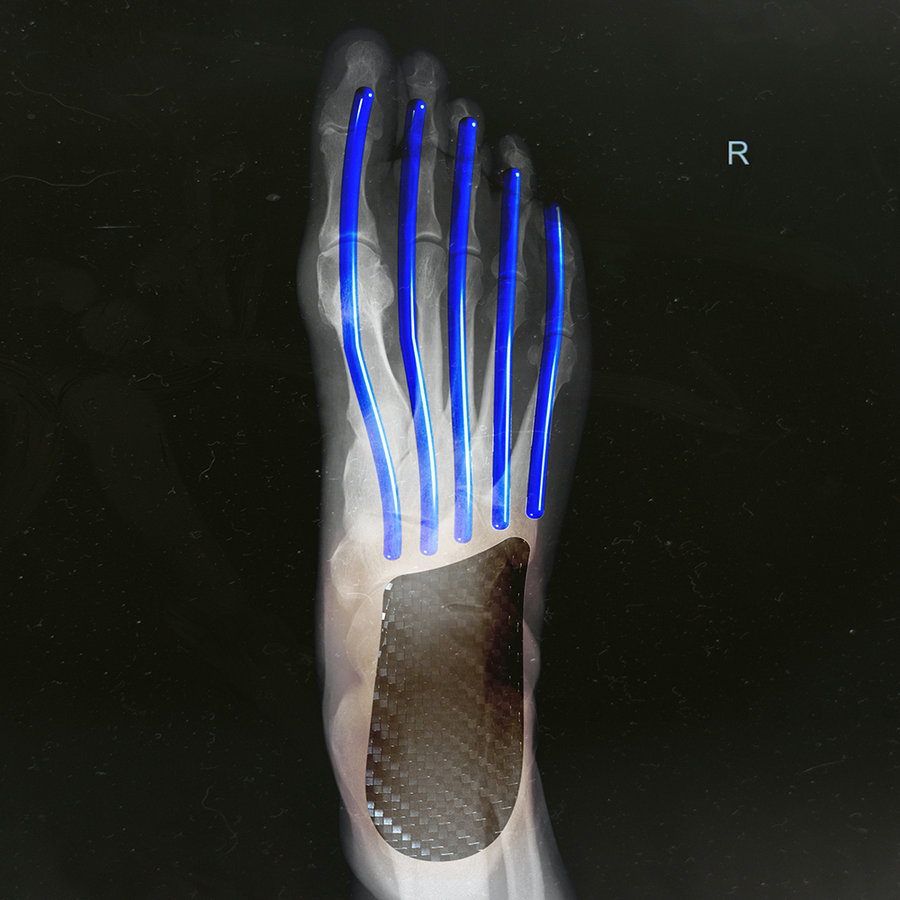

系列标志性的 Energyrods 技术也迭代到 2.0 版本,提供更强的支撑表现和稳定性。

▼ Energyrods 技术